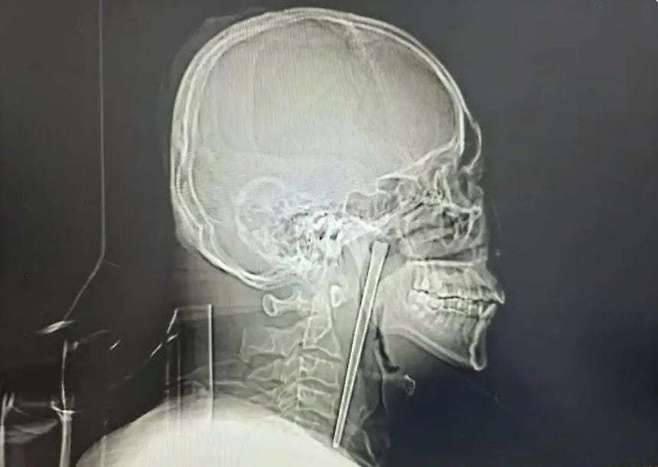

중국에서 한 남성이 길이 12㎝에 달하는 금속 젓가락이 목에 박힌 채로 8년간 생활하다가 뒤늦게 수술로 제거한 사실이 알려졌다.

진료를 맡은 의료진은 검사 결과 그의 연구개(입천장 뒤쪽 부위)에 금속 젓가락이 박혀 있는 것을 확인했다. 다행히 주변 점막이나 장기에는 큰 손상이 없었고, 성대 기능도 정상적으로 유지된 상태였다.

의료진은 환자가 목 절개를 거부했던 점을 고려해 입을 통한 최소 침습 수술을 진행했고, 길이 12㎝의 젓가락을 성공적으로 제거했다. 수술은 소량의 출혈만 발생한 채 비교적 순조롭게 마무리됐으며, 왕 씨는 회복 후 며칠 만에 퇴원한 것으로 전해졌다. 송치훈 기자 sch53@donga.com